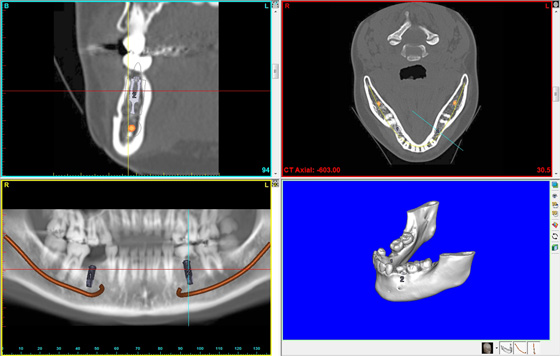

インプラントの難症例

「骨の厚みが足りない」「入れ歯しかできない」といった難症例では、インプラントを行うことが出来ませんでした。

当院では慎重に判断を行い、CT撮影後に顎モデルの作製を行ってから

インプラントの埋入手術を行います。

これにより、飛躍的にインプラント治療が可能になってきました。

●インプラント(下顎・臼歯)

他院にて埋入したインプラントがグラグラすると悩んでいた患者さんが、当院に来院いただいたケースです。

インプラントがグラグラしており、顎の骨もほとんどない状態でした。

このような難症例の場合、より慎重に診断を行い、CT撮影後に顎モデルの作製を行ってからインプラントの埋入手術を行います。